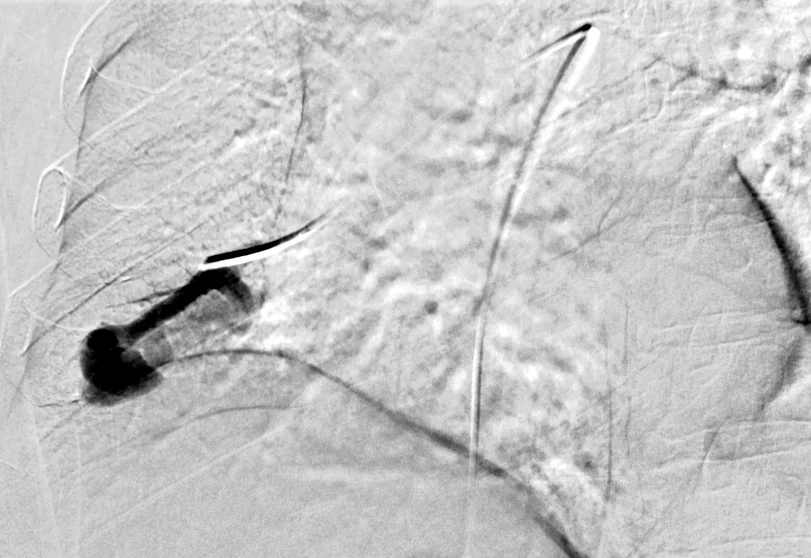

Vascular Malformations: Case 1

40 year old male patient with a history of HHT who presents with an incidentally found pulmonary AVM.